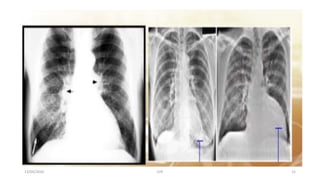

Investigations

• ECG

• 2D echo

• Stress test

• Heart catheterisation

• Chest x-ray

• Blood tests: CBC, BUN, Serum Creatinine ,RBS ,lipid profile ,TSH.

13/04/2020 CHF 15